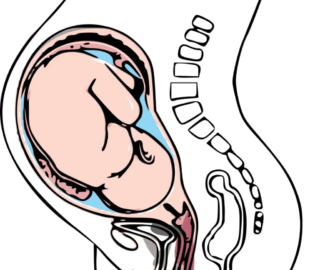

Ačkoli není výskyt spina bifida aperta plodu častý, jedná se o velký problém, který je viditelný již na ultrazvuku prováděném při kontrolách těhotných. Při této